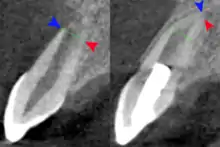

El King's College de Londres publicó en enero de 2017 sobre la regeneración de dentina con esponja de colágeno llenada con glucógeno synthase kinase (GSK-3).[2]